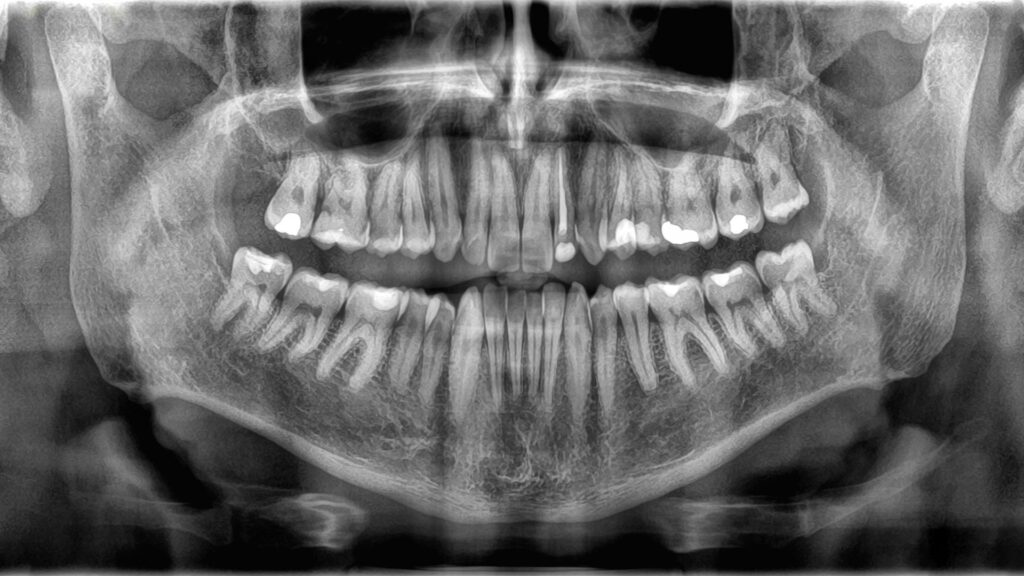

Because bones and teeth do different jobs, they’re also built differently. The outer structure of teeth is called enamel, a thin layer of mineralized tissue. Enamel is the hardest substance in the body — a property it gets from jam-packed crystals made from a compound of calcium and phosphate.

Underneath the enamel lies dentin, a type of mineralized tissue that’s slightly softer than enamel but still hard. Dentin makes up the majority of a tooth’s structure, and it contains tiny tubes that hold blood vessels and nerve endings. The core of the tooth is made of a jelly-like substance called pulp, which houses more blood vessels that provide nutrients to the tooth and to the nerves that control feeling in the tooth.

Bones are covered in a very thin, tough outer layer called the periosteum, which houses both blood vessels and nerves essential for growth and healing in the tissue. The next layer is composed of durable compact bone tissue. The inside of a bone contains cancellous tissue, a sponge-like substance with tiny holes that house bone marrow, where new blood cells are made.